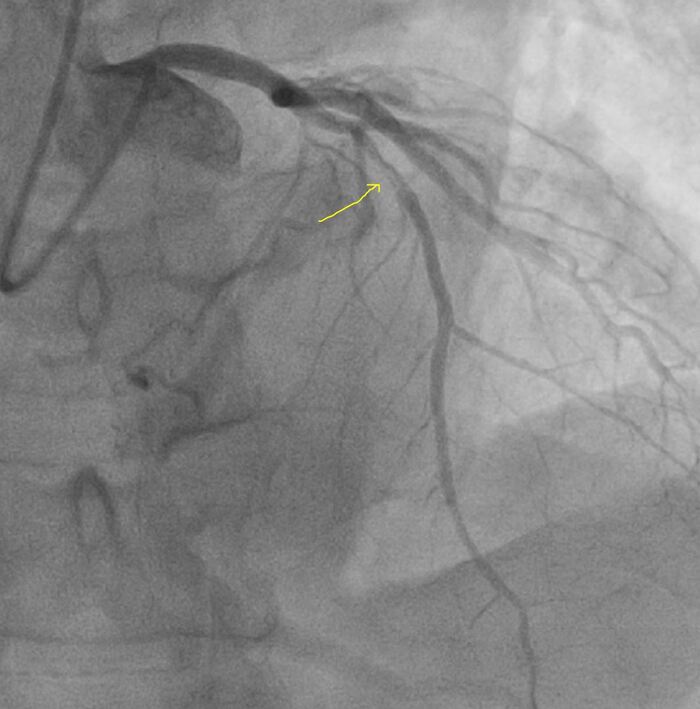

Левая коронарная артерия без поражения

Незначимое поражение правой коронарной артерии